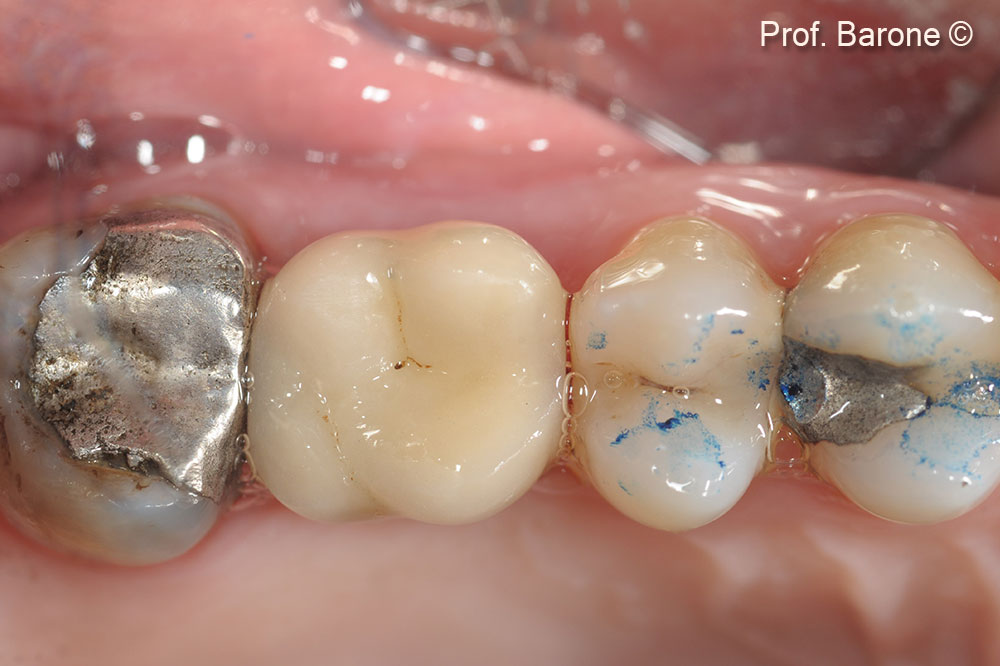

Final restoration, Occlusal View